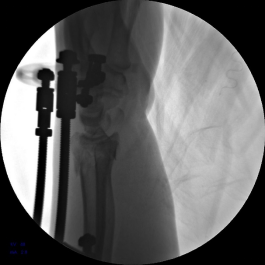

4.安装六轴机器人导向器并包裹无菌巾,摆放合适体位。

5.使用执行器夹持克氏针,于掌侧穿针,撬拨骨块并使用六轴机器人固定针末端以维持撬拨位置。